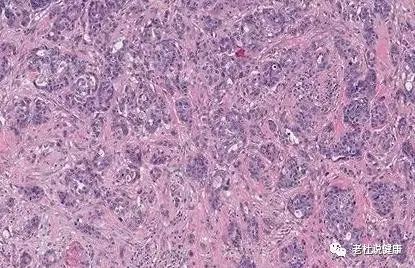

病理示:低分化腺癌。

低分化腺癌,恶性程度高,预后不好